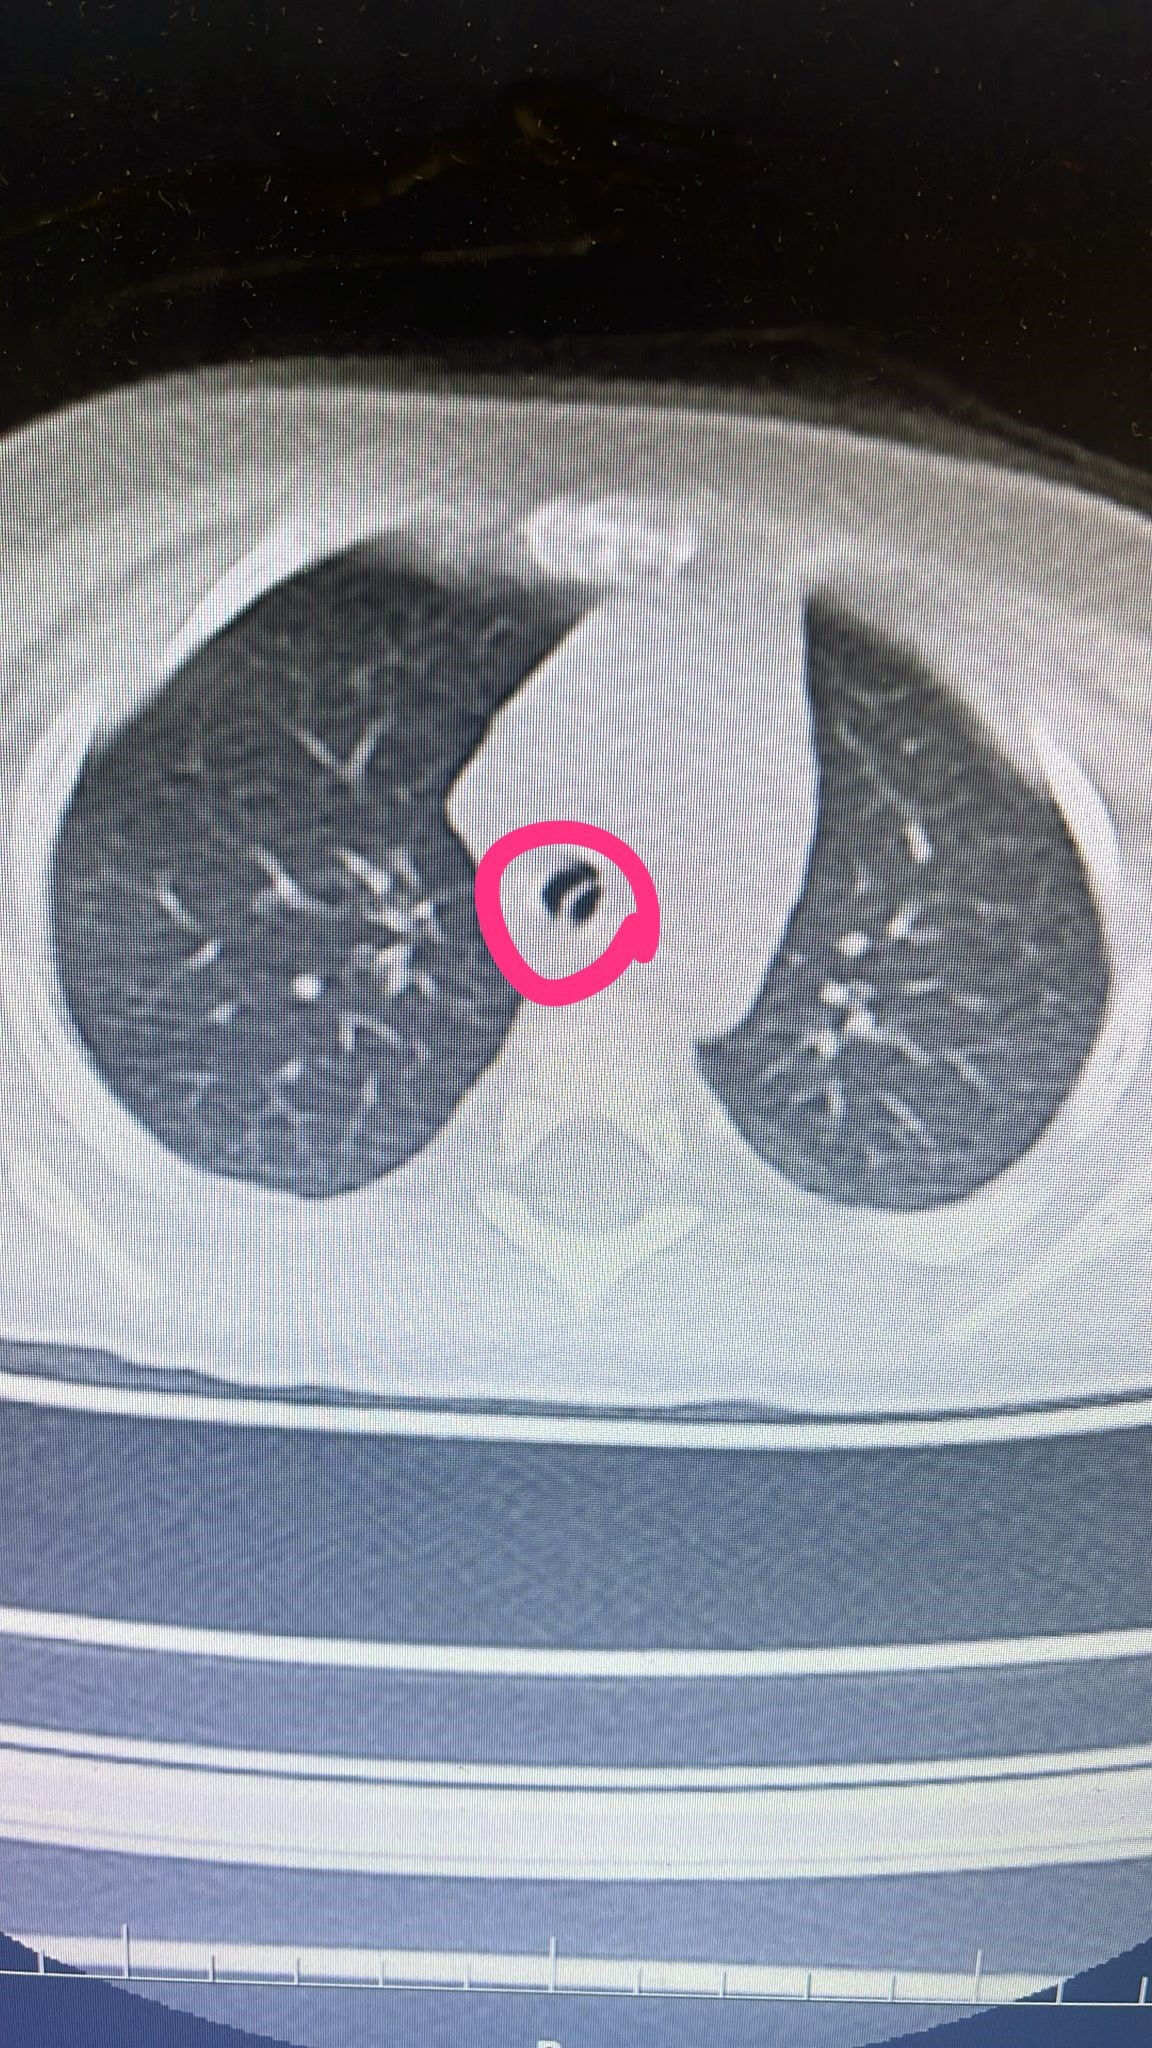

Yapılan tetkiklerde 9 aylık Mine Kavak'ın yuttuğu çekirdek kabuklarından 2-3 tanesinin dik bir şekilde akciğerine saplandığı belirlendi. Batman Eğitim ve Araştırma Hastanesi Çocuk Cerrahisi Doktor Selim Özkaya tarafından ameliyata alınan 9 aylık Mine bebek, bronkoskopi işlemi ile ağız yoluyla ince, ince metal bir kamera tüpü ile akciğerlerine girilerek akciğere saplanan kabuklar çıkartıldı.

Tetkiklerde çocuğun yuttuğu çekirdek kabuklarının hem solunum yolunu kapattığını hem de akciğerlerine saplandığını belirten Doktor Özkaya, yapılan ameliyatın ardından başarılı bir şekilde tamamlandığını söyledi.

Hastanemizin acil servisine yaptıkları başvuruda yapılan tetkiklerinde yutmuş olduğu çekirdek kabuğunun akciğerine kaçtığını tespit ettik. Bronkoskopi dediğimiz işlemi yapmak üzere ameliyathaneye aldık. Ameliyat sırasında 2-3 tane çekirdek kabuğunun akciğerine kaçtığını ve solunum yolunu kapattığını gördük. Yabancı cisimleri temizledik. Ameliyat sonrası hastamızı yaklaşık 12 saat yoğun bakımda izledik. Şuan odaya aldık ve durumu gayet iyi" dedi.